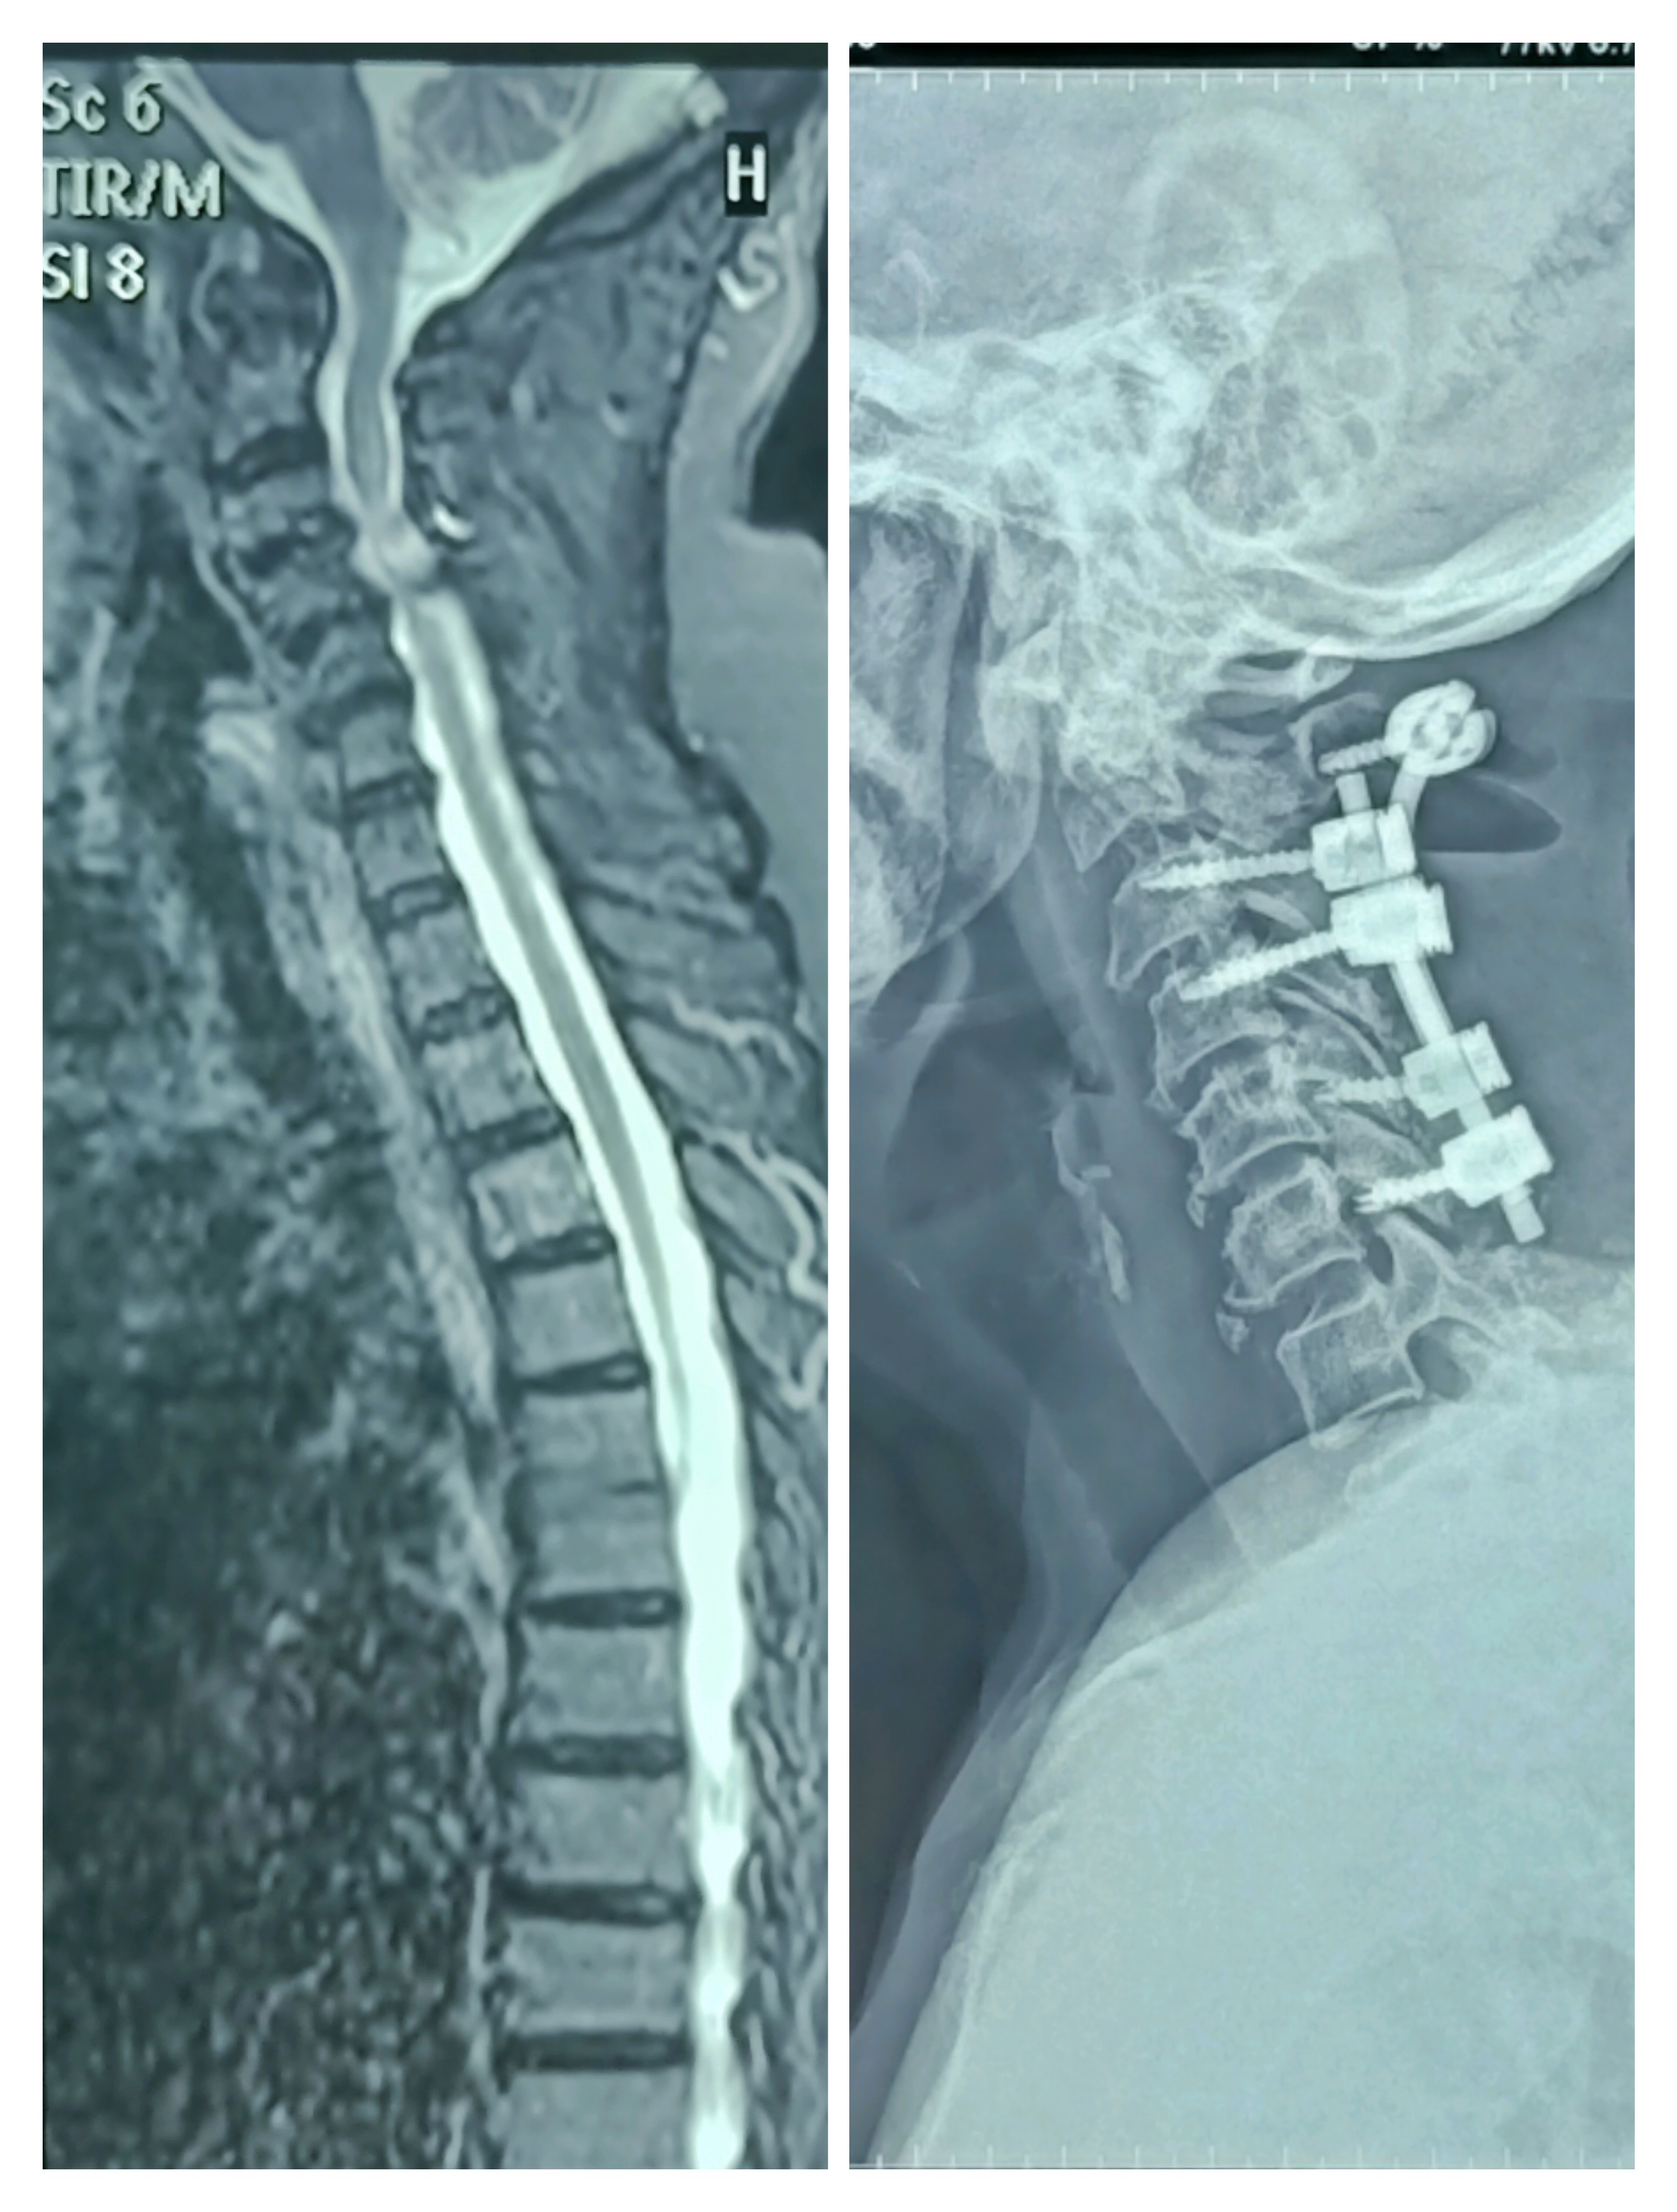

Cervical myelopathy - cervical laminectomy and fix...